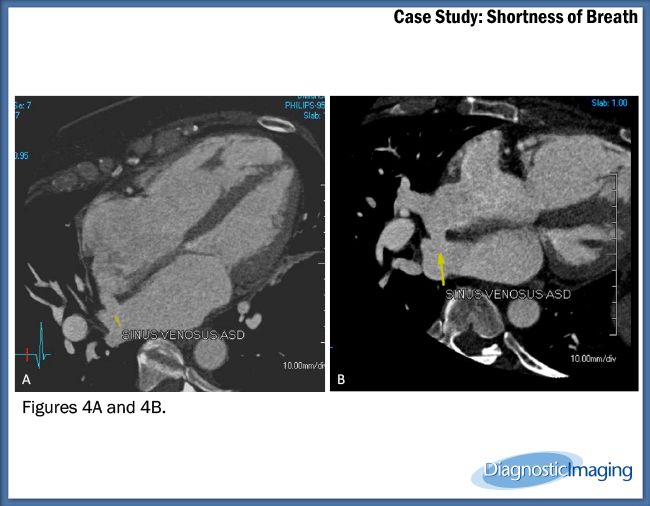

Case History: 60-year-old female with shortness of breath worsening with exertion and fatigue.

Case History: 60-year-old female with shortness of breath worsening with exertion and fatigue. Patient developed intermittent atrial fibrillation and other dysrhythmias and was scheduled for pulmonary vein mapping CTA for planned pulmonary vein ablation therapy.